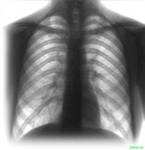

Добавлено: 26.04.2011, 08:53 Источник: http://www.tubunet.ru автор: администратор ![]() Причиной повсеместного распространения туберкулеза является его инфекционная природа. О заразности этого заболевания было хорошо известно врачам и ученым древнего мира. В своде законов Хаммурапи закреплялось право на развод с женой, заболевшей туберкулезом, а по кодексу Ману, принятому в Древней Индии, запрещалось брать замуж женщин, в семьях которых было подобное заболевание. В Древней Персии изолировали больных не только проказой, но и чахоткой. В Испании, Португалии, в Венеции и Неаполе XVIII века нашей эры действовали законы, предписывающие врачам сообщать обо всех случаях заболевания легочной чахоткой. Таких больных госпитализировали, а их одежду и домашнее имущество уничтожали. За нарушение этих законов предусматривалось суровое наказание. Даже в середине XIX века известного польского композитора Фредерика Шопена, отправившегося лечиться от туберкулеза в Испанию, не пустили на пассажирский пароход в порту Майорка. Хозяин гостиницы в Барселоне распорядился сжечь все вещи и мебель в номере, где остановился больной Шопен, отнеся все убытки на его счет. Научные доказательства заразности туберкулеза были впервые получены в 60-х годах XIX века французским врачом Ж. Вильменом, заметившим, что после появления на военном судне, где он служил, больного чахоткой вспыхнула эпидемия этого заболевания среди матросов. Вильмен провел серию опытов на кроликах и морских свинках, которым вводил кровь больных или заставлял дышать распыленной мокротой своих пациентов. При этом животные гибли от заболевания, очень похожего на туберкулез у человека. Однако заслуга открытия возбудителя туберкулеза принадлежит немецкому бактериологу Роберту Коху, в честь которого этот возбудитель и получил наименование «бацилла Коха» (БК). Особенности развития заболевания, длительное течение и повторные обострения в значительной степени связаны с биологическими особенностями вызывающего его микроорганизмам. В медицинской литературе его обозначают также как «микобактерии туберкулеза» (МБТ). Само название указывает на принадлежность возбудителя к роду микобактерий, широко распространенному в природе. Многочисленные виды микобактерий, совершенно безвредны для человека, обитают в почве и воде. Некоторые из них вызывают заболевания у рыб, пресмыкающихся и птиц, но возбудителями туберкулеза у людей являются только два из них — микобактерии человеческого и бычьего типов. Под микроскопом они имеют вид палочек, обычно с искривленными неровными контурами и зернами внутри. Различить МБТ человеческого и бычьего типов удается только с помощью специальных микробиологических и биохимических тестов. Характерными особенностями обоих типов возбудителя является их высокая устойчивость к вредным воздействиям внешней среды. Особая липидная оболочка микобактерий делает их не чувствительными к действию спиртов, кислот и щелочей, они хорошо переносят длительное высушивание и замораживание. В уличной пыли этот микроорганизм остается жизнеспособным до двух недель, а на страницах книг — до трех месяцев. В темных серых помещениях, например в подвалах, микобактерии могут сохраняться и более долго. Кипячение, прямое солнечное или ультрафиолетовое облучение, хлорамин, хлорная известь и другие сильные антисептики убивают микобактерии туберкулеза. Эти средства обычно и используют при дезинфекции. При выращивании на специальных питательных средах и в живом организме МБТ проявляют удивительную изменчивость и приспособляемость к неблагоприятным воздействиям. При этом они могут терять оболочку, приобретать шарообразную или зернистую форму, становясь недоступными для действий лекарственных препаратов или естественных механизмов защиты человека. Подобные превращения микобактерий, вполне естественны для данного рода микроорганизмов, обозначаются как L- цикл их эволюции. Переход микобактерий в так называемые L-формы позволяет им годами и десятилетиями незаметно существовать в условиях живого организма, не вызывая никаких недомоганий. Но при этом постоянно сохраняется опасность, что они вновь трансформируются в обычные микобактерии и вызовут повторное заболевание туберкулезом. Подобная способность возбудителя объясняет, почему инфекция, однажды попавшая в организм человека, может сохраняться (персистировать) на протяжении многих лет или даже всей жизни, не сопровождаясь никакими нарушениями. Но в неблагоприятных условиях, например, например, при ослаблении сопротивляемости в результате самых различных причин, персистирующая инфекция способна проявить себя и вызвать серьезное заболевание. Микобактерии вызывают туберкулез не только у человека и крупнорогатого скота, но и у кошек, собак, свиней, приматов, буйволов, а также у большинства диких млекопитающих. Примечательно, сто туберкулез у животных чаще вызывается бычьим типом возбудителя, хотя в полнее возможно и заражение домашних животных от больных людей. В последнее время внимание ученых привлекает гипотеза о сравнительно недавнем возникновении микобактерий человеческого типа в результате мутации возбудителя бычьего типа, существовавшего в природе задолго до появления человека. Но в любом случае незыблемым остается основное положение, сформулированное еще Робертом Кохом: «Без туберкулезной бациллы не может быть туберкулеза». Как происходит заражение туберкулезомГлавным источником распространения инфекции является больной туберкулезом человек, выделяющий с мокротой возбудителей заболевания. При кашле, чихании, смехе, даже при разговоре мелкие капельки слюны и мокроты рассеиваются в окружающем воздухе на расстояние до 1,5 метров и могут удерживаться в нем до 30–60 минут. В таких капельках нередко и содержаться микобактерии туберкулеза. Вместе с вдыхаемым воздухом они проникают в легкие окружающих людей. Воздушное распространение инфекции может происходить и несколько по-иному. Капельки мокроты, оседая на одежде, белье больного, на полу и мебели его комнаты, высыхают и смешиваются с пылью. Вытряхивание такого белья в помещении, неаккуратная сухая уборка сопровождается подъемом пыли, в которой сохраняются вполне жизнеспособные микобактерии, попадающие затем в дыхательные пути окружающих. Значительно реже человек может заразиться от больных туберкулезом домашних животных, обычно при употреблении в пищу непастеризованного молока или непроваренного мяса больных коров. При подобном пути заражения возбудители, содержащиеся в принятой пищи, проникают в организм через миндалины или стенки кишечника, попадая в ближайшие лимфатические узлы, а затем и в ток крови. Известны и другие, еще более редкие пути заражения, например через царапины и ссадины на коже. Это возможно при крайне низком уровне гигиены, когда мокрота или гнойное отделяемое из туберкулезных свищей сохраняются на одежде и белье, которыми пользуются как больные, так и здоровые люди. |